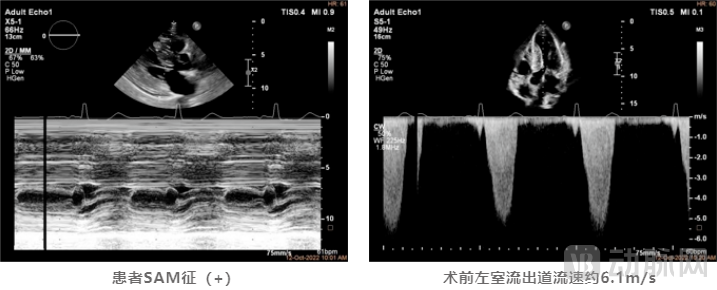

患者为65岁女性,1年前出现胸闷、气促加重、伴夜间阵发性呼吸困难等现象,药物治疗后症状仍未缓解。患者心脏彩超提示:LVEDD 42mm, LAD 36mm,EF 65%。室间隔非均匀性显著增厚,最厚处厚度22mm,左室后壁增厚为14mm,左室流出道梗阻(重度),见SAM征阳性。伴有二、三尖瓣轻度反流,主动脉瓣钙化并轻度反流。LVOT收缩期流速明显增快,约6.1m/s,PGmax高达150mmHg。

术后彩超提示SAM征消失,二尖瓣反流改善,LVOT收缩期流速由术前6.1m/s降低至术后2.1m/s,左室流出道峰值压差更是从术前的150mmHg下降至17mmHg,术中即刻消融效果使得流出道压差减小量高达133mmHg。